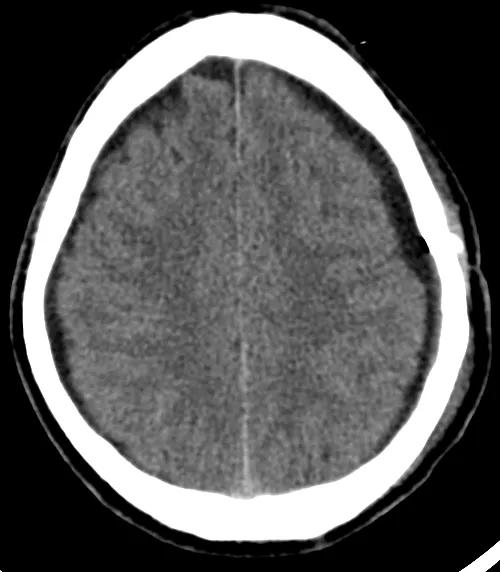

术前CT示:左侧额颞顶部慢性硬膜下血肿。

术后CT示:血肿引流冲洗满意,脑组织较前复张。